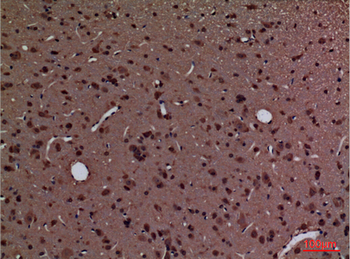

Anti-Cyclophilin A/PPIA Antibody [orb19174]

FC, ICC, IF, IHC, IHC-Fr, WB

Human, Mouse, Rat

Rabbit

Polyclonal

Unconjugated

10 μg, 100 μgCYPA Rabbit Polyclonal Antibody [orb100498]